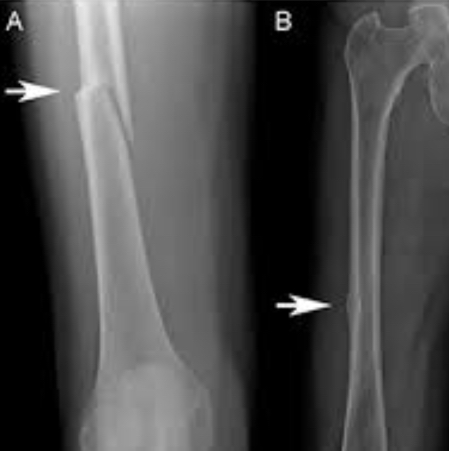

Fracture Atypique

- Les Patients sous biphosphonates chroniques ou Denosumab peuvent faire des fractures diaphrasaires fémorales sur des mouvements peu importants

- Peut avoir deja un aspect de fracture incomplet en regardant d’anciens clichés